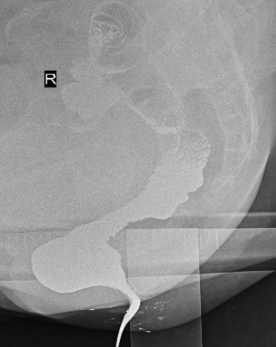

精准诊断:排粪造影——动态还原排便过程!对于疑似出口梗阻型便秘的患者,方松山主任首选的检查是排粪造影,排粪造影是检验出口梗阻型便秘的金标准。他形象地比喻:“这就像给排便过程拍电影,而不是只拍一张照片——只有动态观察,才能发现那些静态检查看不到的问题。”

现场直击:影像科的显示器上,正在播放一段动态画面。这是患者模拟排便过程的X线造影检查,能清晰地看到直肠、肛管的形态变化。